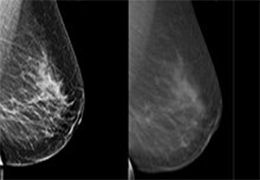

View X-Ray CT & MRI Scans Fast and Easily

Designed for surgeons, Pro Surgical 3D makes it easy to view patient scans quickly. Pro Surgical 3D facilitates the optimal 3D treatment and assessment workflows based on X-ray CT and MRI scans – and best of all, it’s FREE!

Everyone – including surgeons, patients and their loved ones – benefits from being better informed by the wealth of information buried within CT and MRI scans. Pro Surgical 3D gives surgeons more information to develop optimal treatment plans for patients. It also helps patients and their support group better understand their medical condition and proposed treatment options.

Designed mainly for CT and MR DICOM modalities.

Side-by-side comparative assessment for pre- and post-operative scans.